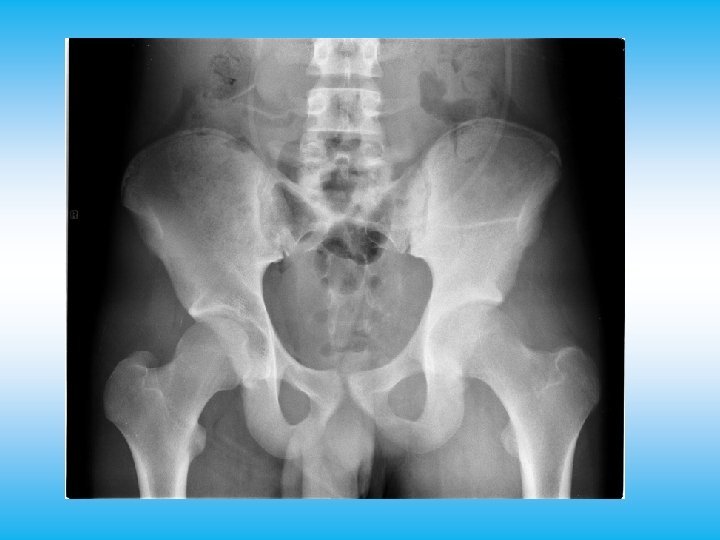

David 17 aa • Da 3 mesi, dopo caduta da bicicletta con trauma all’anca sx, dolore in regione inguinale con zoppia esacerbato dallo sforzo; ecografia anca negativa, rx con lieve riduzione in ampiezza della coxo-femorale • persistenza del dolore che è divenuto continuo nuova radiografia del bacino • A livello inguinale sx e coscia medialmente palpabile tumefazione di consistenza dura a margini sfumati, fissa • Emocromo nella norma, VES 15, LDH 716 • RNM: . . diffusa omogenea alterazione dell’emibacino sx che risparmia solamente il versante sacrale dell’articolazione sacro-iliaca, capta mdc ed è circondata da manicotti di tessuto solido